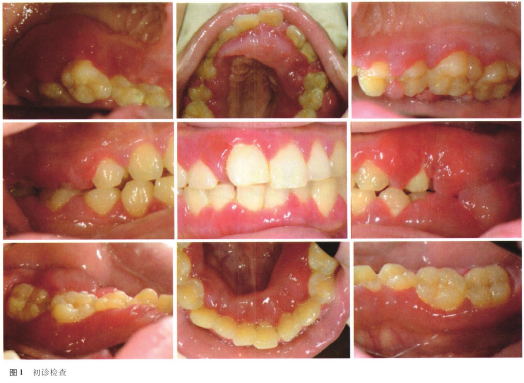

计划进人牙周手术阶段。等离子刀切除上、下颌颊舌侧增生牙龈组织,暴露牙列唇舌面,修整牙龈外形,牙周塞治剂覆盖创面。术后2周牙龈形态基本正常,如图4。